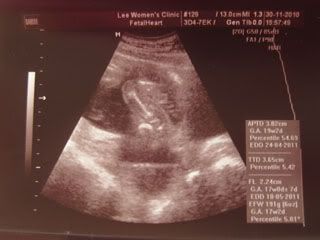

Her tighs and private part.